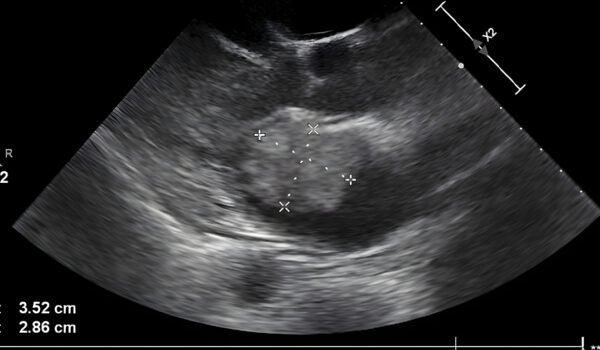

In what many are calling a modern-day miracle, Kentucky mother Amanda Foster has captured hearts worldwide with a story that blends faith, hope, and resilience. At 33, Amanda shared an ultrasound image that seemed to show something extraordinary: a hand cradling her unborn baby boy, Kyler. Social media quickly went viral, as thousands celebrated what Amanda describes as the “hand of God” protecting her child.

Despite anxiety and past trauma, Amanda turned to faith. Before every ultrasound, she prayed for Kyler, asking for protection and guidance. And during one scan, her youngest daughter, Bailey, noticed something remarkable in the black-and-white image. To Amanda, it looked like a divine hand cradling Kyler’s head—a visual reassurance after years of heartache.